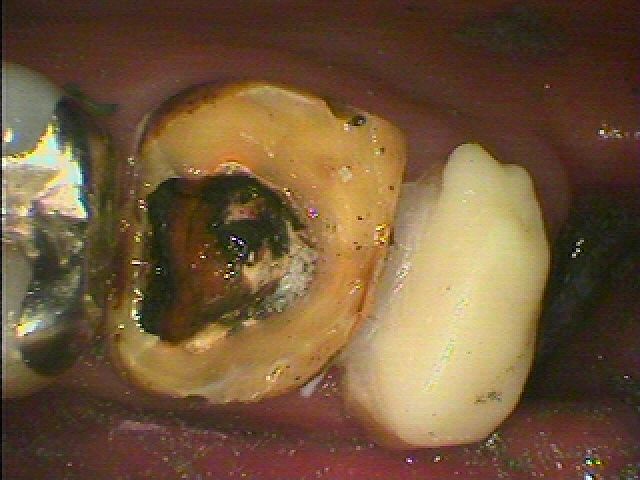

7番は大きく虫歯となり歯が半分になっています。

8番は歯なのかどうかも分かりにくいくらい保存不能の状態です